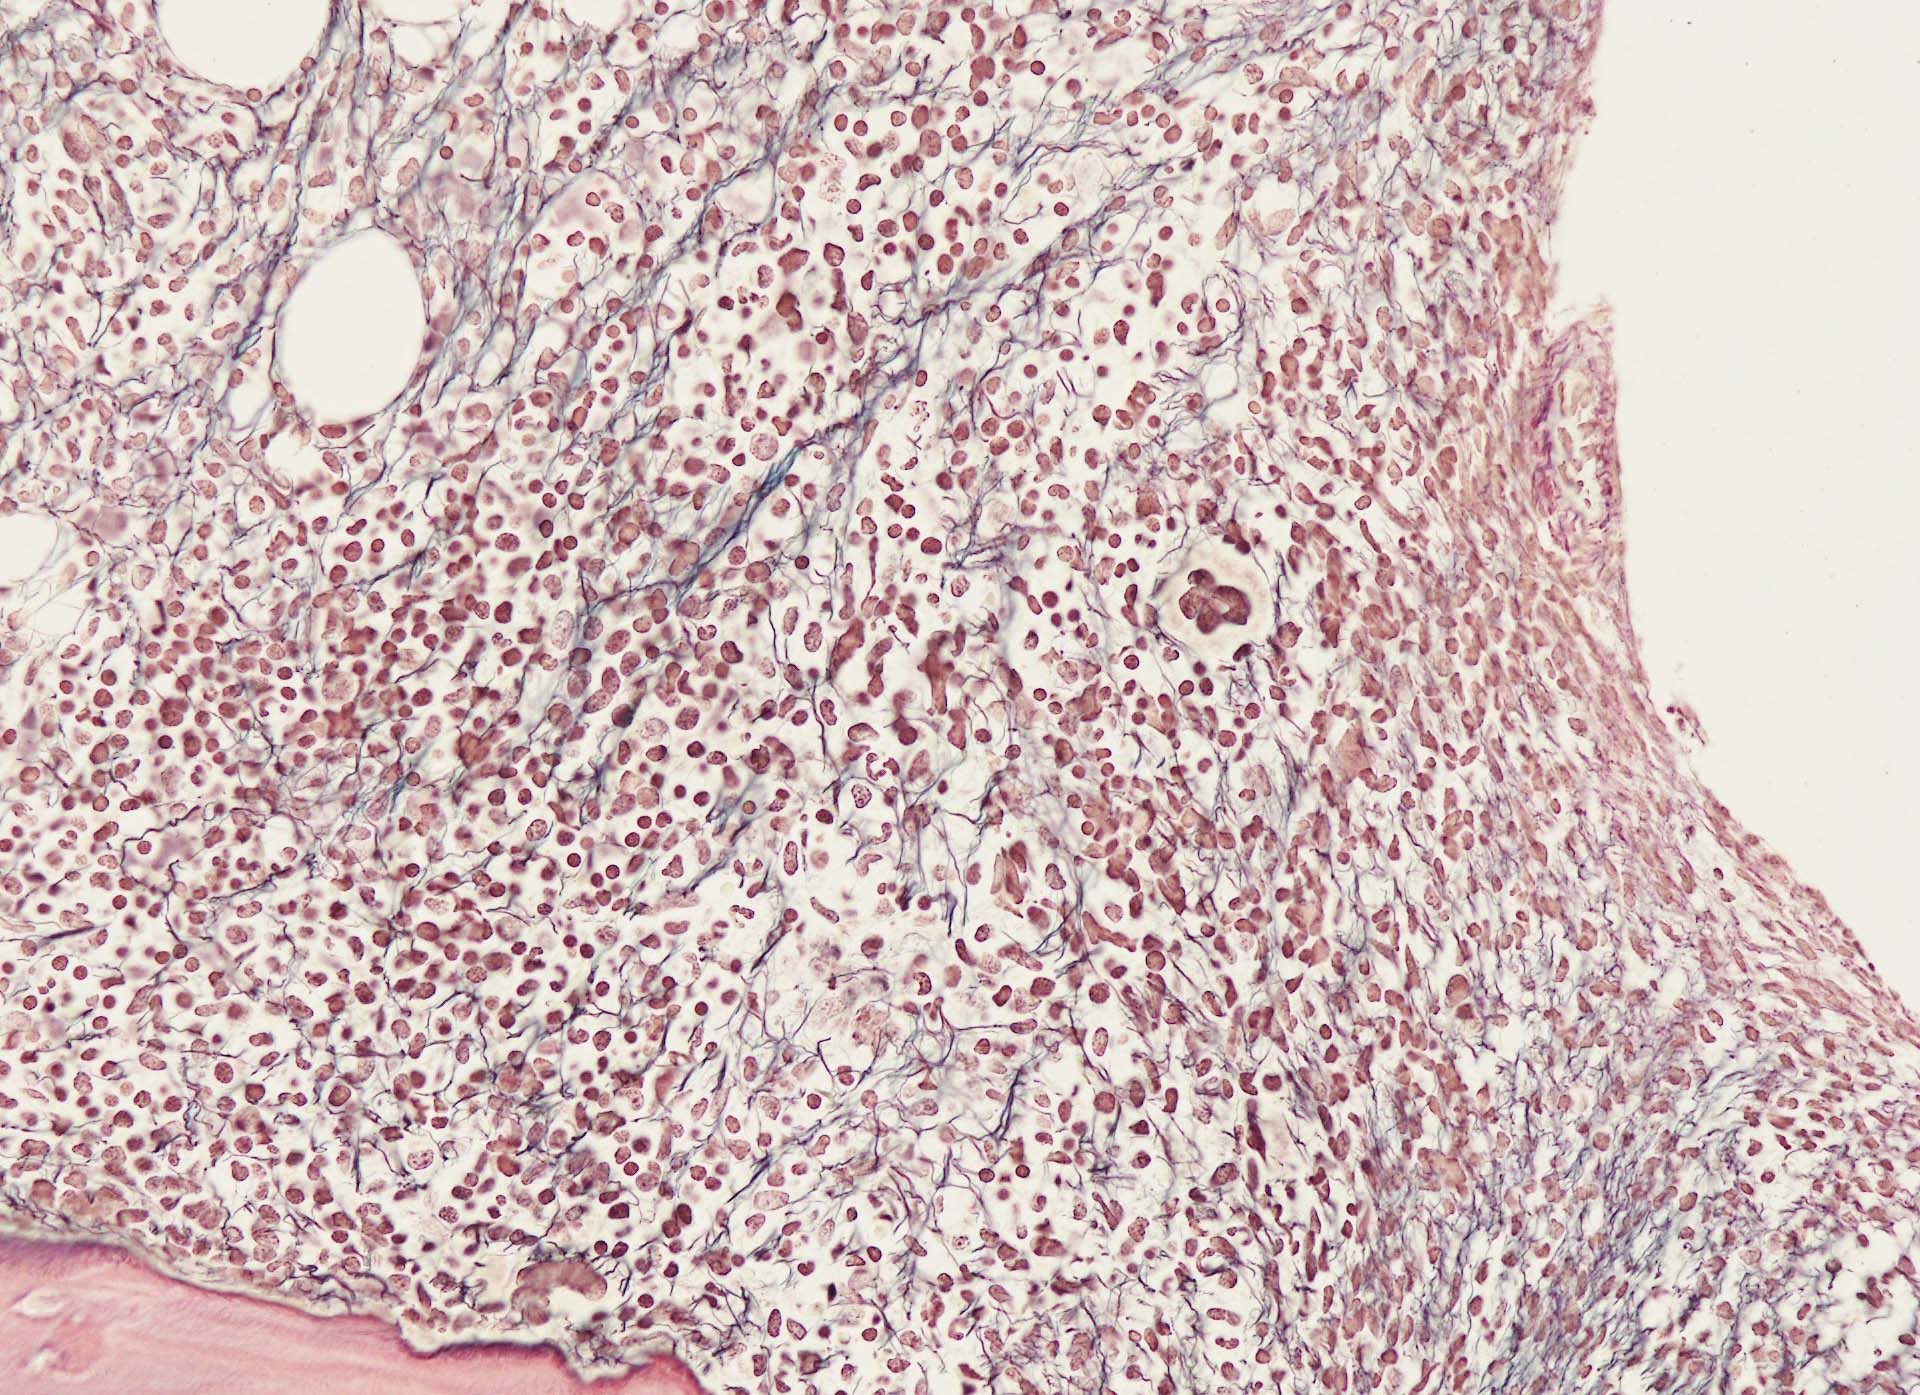

Hairy-FCM のコピー.jpg ASD-up-PAX5ok.jpg びまん性にPAX5陽性の小型B-cellsが増殖している.

増殖細胞はCD20(相変わらずべったり染まる), CD19, PAX5陽性 CD25陽性.